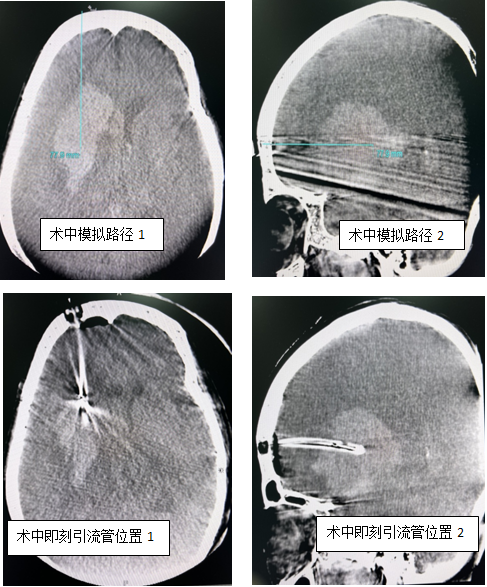

患者85岁高龄,以“突发意识不清2小时”代主诉入院,急诊行头颅CT平扫示右侧额颞叶、基底节区脑出血,量约50ml。李帅主治医师急会诊后收入神经外科神经监护室完善术前准备,给予控制血压、脱水降颅压、止血抑酸等对症处理。患者病后意识不清,颅内出血量大且中线偏移明显,手术指征明确。但考虑到患者高龄、既往基础疾病较多,传统的气管插管全麻和开颅清除血肿手术风险较大、术后可能拔管困难,经科室术前讨论,决定利用黑料网先进的复合手术室,使用局部浸润麻醉、术中CT引导、经眶上(血肿纵轴)行颅内血肿钻孔引流术。手术当日,患者仰卧位行DynaCT评估并模拟穿刺路径、方向及深度,标记右侧眶上约3cm长切口,切开皮肤后颅骨钻小孔并切开硬膜,按预先模拟路径将引流管穿刺至血肿中心部位,再次行DynaCT明确引流管位置,缓慢抽吸出约25ml暗红色血肿,留置引流管于血肿腔并固定,术后持续引流5天后复查示大部分血肿消失,给予拔出引流管,患者恢复顺利,已转至普通病房继续对症治疗。